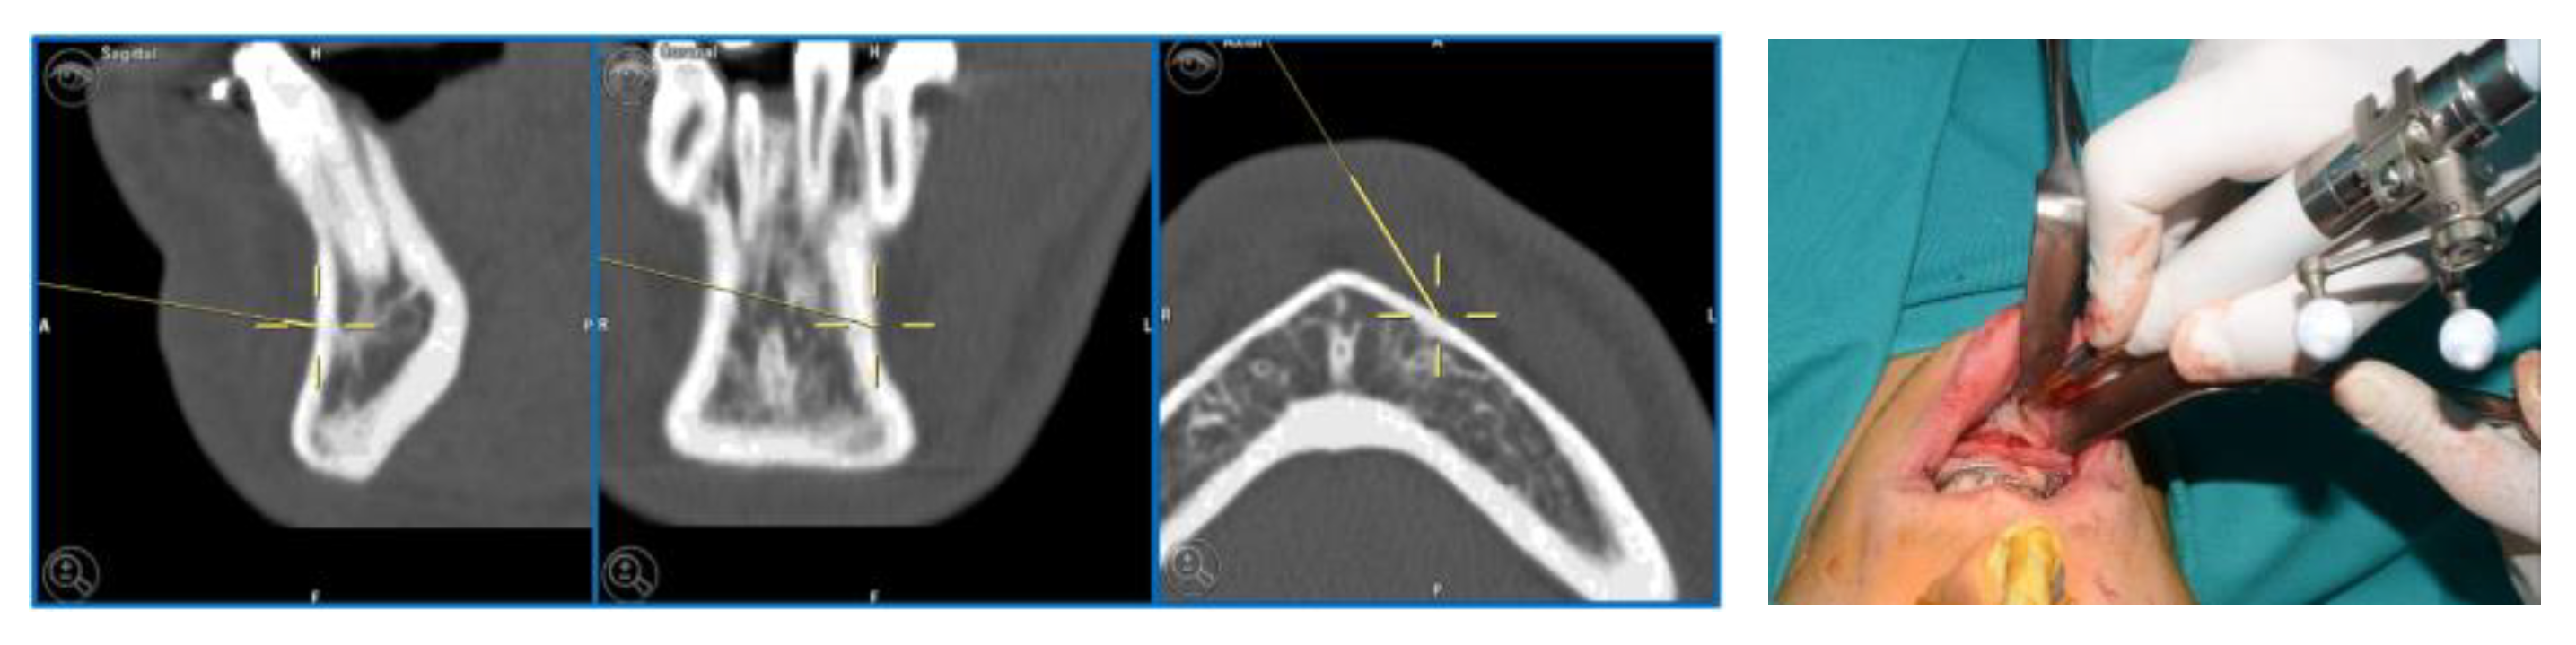

The piezoelectric tool was registered by anchoring the three reflective spheres to the tool’s handpiece. At the same time, the tip of the piezoelectric device was marked and used as a reference for navigation (Figure 9).

Figure 9.

Registration of the piezoelectric tip and connecting it to the navigator with a calibration matrix.

The navigation accuracy was less than 1 mm. The subapical osteotomy was performed as previously planned (Figure 10).

Figure 10.

Surgical navigation and Subapical osteotomy (Köle) with tracked piezoelectric device.